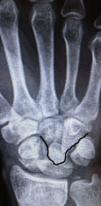

El síndrome de Fenton puede ir asociado a otras fracturas-luxaciones complejas del carpo17, de la extremidad distal del cúbito y radio18, así como también en niños19 e incluso puede ser bilateral13. Sea como fuere, el síndrome de Fenton es de difícil diagnóstico, fundamentalmente por la rotación extrema que sufre el fragmento proximal del hueso grande. En este contexto, hay que estar muy atentos a la hora de valorar las radiografías. Para ello, es preciso la identificación de los 3 arcos carpianos de Gilula20. El arco I está formado por los márgenes de las superficies proximales del escafoides, el semilunar y el piramidal; el arco II lo forman los márgenes de las superficies distales de los mismos huesos; y el arco III lo forman los márgenes de las superficies proximales de los huesos grande y ganchoso. En el síndrome de Fenton, el arco III queda totalmente alterado, indicando la presencia de lesión de la articulación mediocarpiana (fig. 5).

Alteración del arco III de Gilula20 en la proyección anteroposterior de un paciente con síndrome de Fenton.